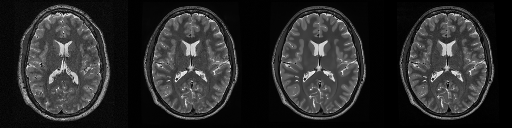

HCP T2w dataset

We utilize images from the publicly available Human Connectome Project (HCP) [51] T2-weighted (T2w) images dataset for the task of compressed sensing, which contains brain images from 47 patients. The HCP dataset includes cross-sectional images of the brain taken at different levels and angles.

Compressed sensing

We train a flow-based model from scratch on 10,000 randomly sampled images, utilizing the ncsnpp architecture [9] with minor adaptations for grayscale images. We employ compression rates , meaning . The measurement operator is given by a subsampled Fourier matrix, whose sign patterns are randomly selected. We evaluate our reconstruction algorithm’s performance on 200 randomly sampled test images.

We present the quantitative and qualitative results of compressed sensing in Tab. 1 and Fig. 4, respectively. As shown in Tab. 1, our method consistently achieves the best performance across varying compression rates . In Fig. 4, our method produces reconstructions that are more faithful to the original images, with fewer artifacts, leading to higher accuracy and clearer details.